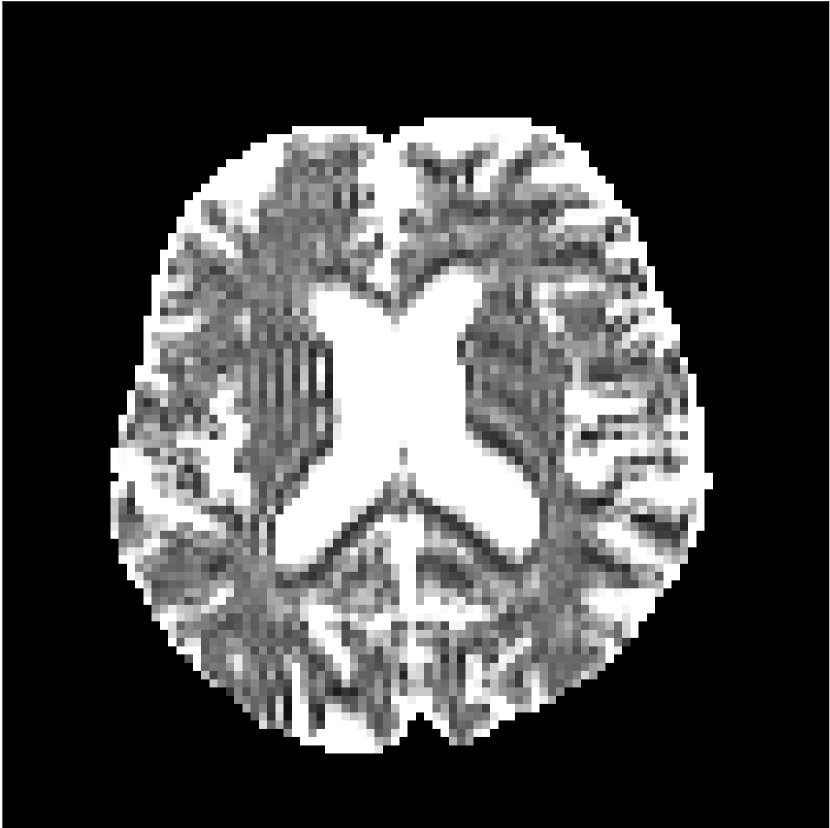

Figure 8 shows examples of non-diffusion-weighted images before and after processing. The raw images (Raw) served as the input for the magnitude deep learning (MCNN) and complex deep learning (CCNN) methods.

Raw

MCNN,

MCNN Resid.,

CCNN,

CCNN Resid.,

No PF

5/8 PF

Both methods remove artifacts, but the MCNN method allows residual rippling artifacts to pass through in the presence of partial Fourier. These rippling artifacts are not present in the CCNN method.